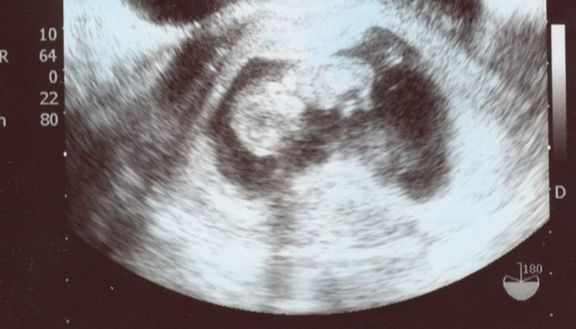

"おなかの中はどうなっていくの? エコー写真で振り返る、高齢ママのはじめての妊娠生活" -

緊急帝王切開で誕生。エコー写真で綴る息子と過ごした252日 -

不妊治療や2度の流産経験を経て「初めての出産」。日々成長する胎児の記録をエコー画像で振り返る -

待望の妊娠判明!エコー写真に見る、我が子を胸に抱くまでの“命の軌跡275日” -